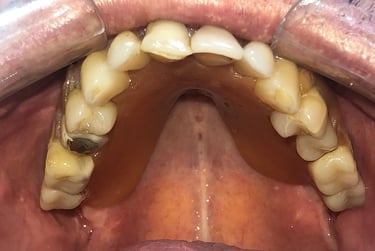

Aspecto Clínico Inicial - Fotografias originais — nenhuma contém retoques

Implantes perdidos por peri implantite - Imagens originais — nenhuma contém retoques

Implante feito por outro profissional há cerca de 5 anos desenvolveu inflamação, saída de pus e gengiva inflamada, indicando peri-implantite, uma infecção que pode comprometer o implante se não tratada.